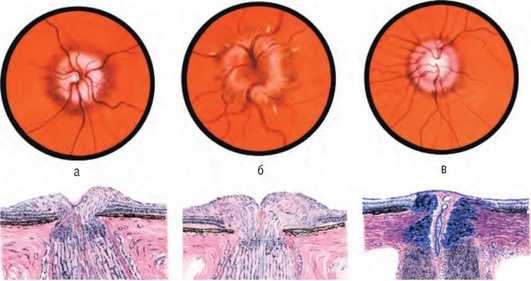

Рис. 12.2. Состояние диска зрительного нерва и его офтальмоскопической картины: а - в начальной стадии застоя - незначительный отек диска, расширение вен сетчатки; б - в стадии кульминации застоя - резкий отек диска с кровоизлиянием по краям, выраженное расширение и извитость вен; в - в стадии вторичной атрофии - диск уменьшается в размере, бледнеет, границы долго остаются нечеткими, вторичная (после застоя) атрофия диска зрительного нерва